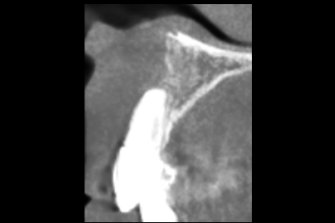

多発性歯根嚢胞を精密根管治療、歯根端切除術を行なった症例

治療後

| 治療内容 | ラバーダム、マイクロスコープ、 MTAを用いた精密根管治療 歯根端切除術 |

歯の保存、嚢胞の摘出